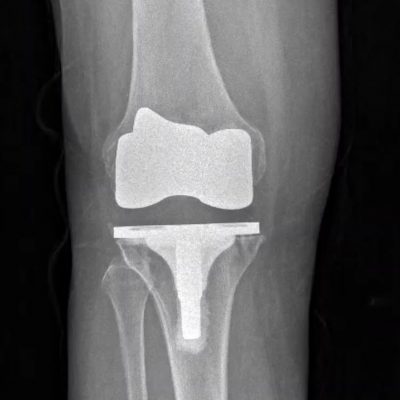

Knee replacement surgery is a common procedure to relieve the pain and disability caused by joint osteoarthritis. During knee replacement surgery, the damaged bone and cartilage are removed and replaced with an artificial joint.

This patient-specific data helps establish boundaries for the handpiece so that the damaged surfaces of the knee can be removed, the joint can be balanced, and the implant can be put in with greater precision.

Recovery will likely vary from patient to patient, however, due to the unparalleled precision provided by this improved technology, we are able to more accurately balance the knee and placement of components specific to your unique anatomy. Although the studies are still limited, it is thought that better placement of the components may lead to less wear and future failure. Ultimately, the goal of joint replacement is to restore your normal anatomy as best as we can and robotics allows me to have precision and accuracy in creating a knee tailored to you.